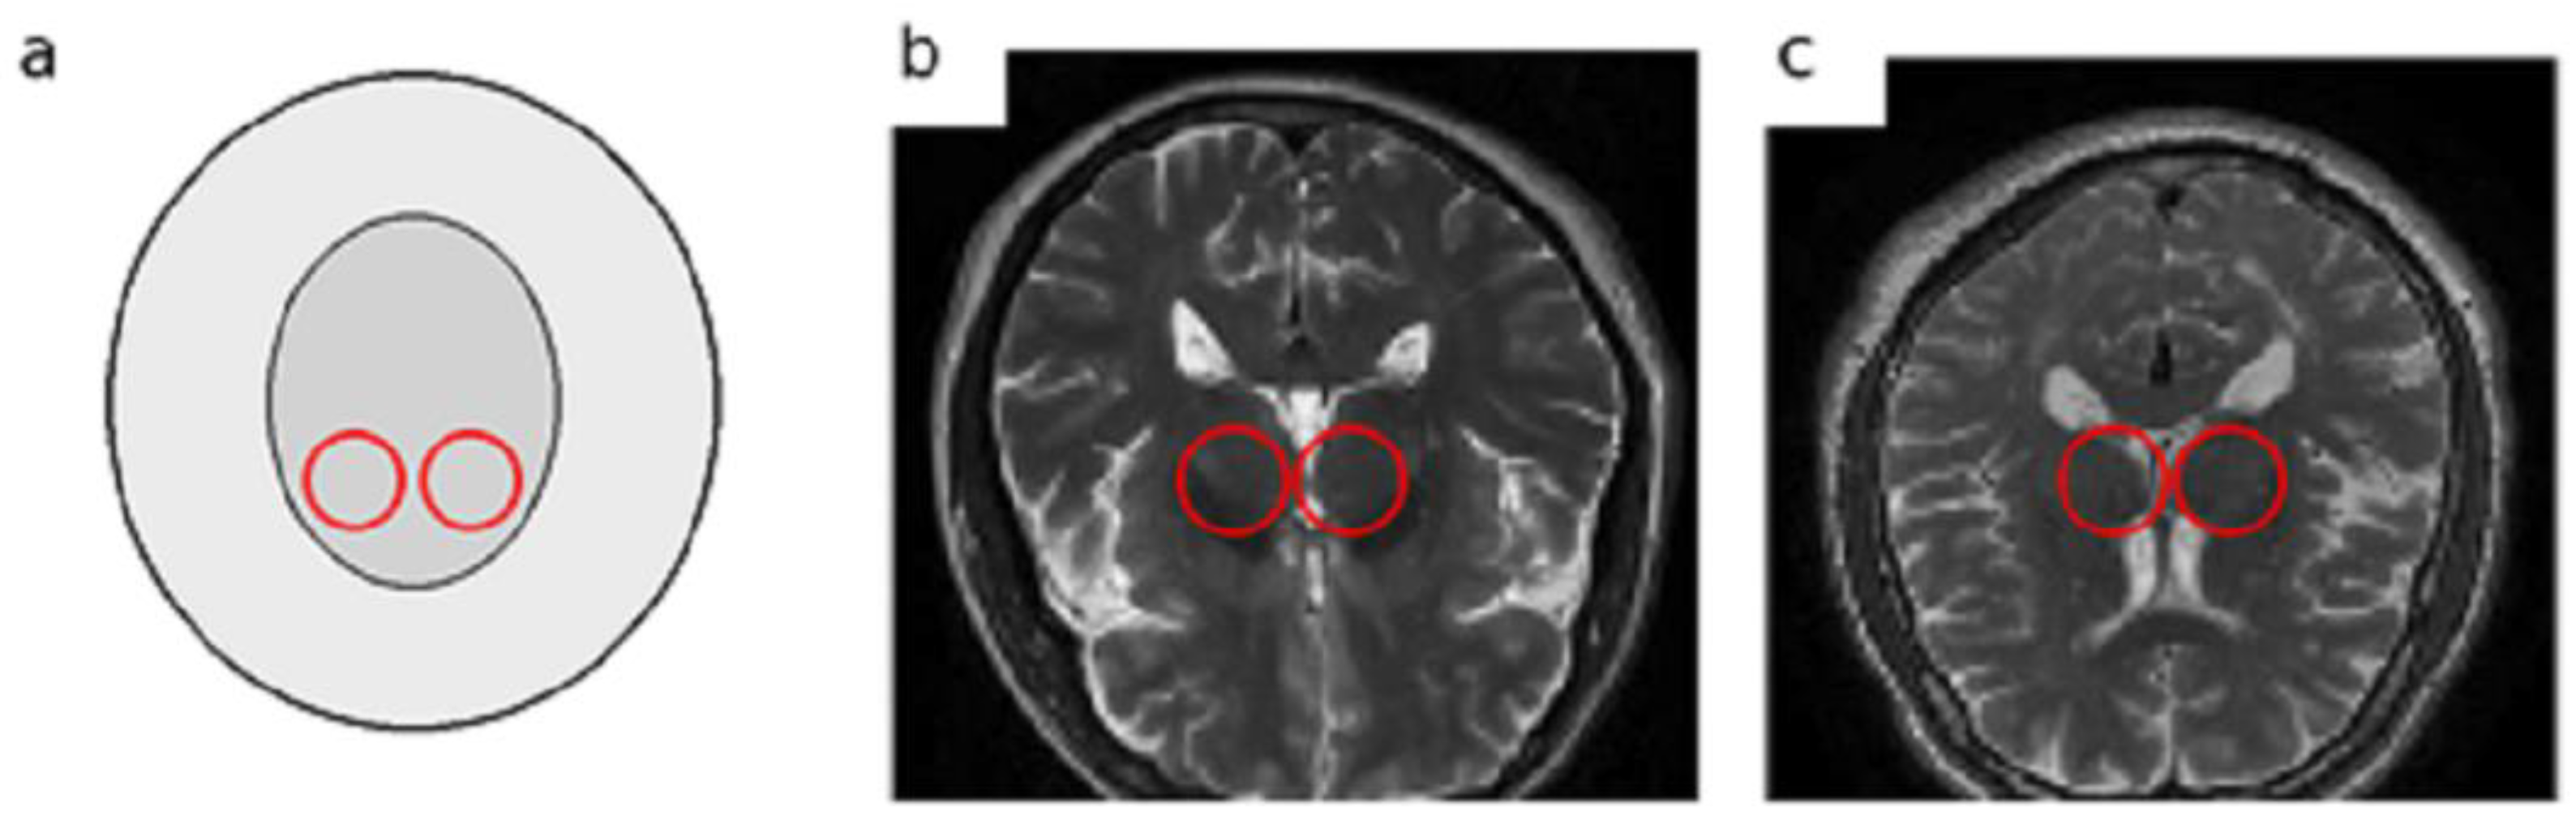

In the early stages of PD, non-motor symptoms overlap with other neurological diseases like Multiple System Atrophy (MSA) or drug-induced Parkinsonism, the clinical diagnosis faces serious challenges [6,7]. These non-motor symptoms, including sleep disturbances, depression, olfactory dysfunction, and subtle cognitive changes, are often nonspecific and can lead to misdiagnosis or delayed diagnosis even by experienced clinicians [8]. MRI plays a vital role in assessing and monitoring structural and functional changes in the brain. It offers a non-invasive, safe, and cost-effective technique. T2-weighted MRI images, owing to their high contrast between grey and white matter and sensitivity to tissue changes, allow clear visualization of subcortical structures such as the SN and basal ganglia. These characteristics make T2-weighted MRI particularly suitable and widely employed in studies of PD [9]. Despite the potential of MRI for detecting structural brain changes, reliably identifying subtle nigral alterations in early-stage Parkinson’s disease remains highly challenging. Manual or semi-quantitative MRI assessments are prone to considerable diagnostic errors, reported to be ≥25. Furthermore, subtle structural changes in the substantia nigra and basal ganglia are often difficult to distinguish from normal ageing, resulting in significant inter-observer variability. These limitations highlight the need for automated, objective, and reproducible approaches capable of detecting fine-grained nigral changes that often escape human visual perception [10]. To better illustrate the anatomical target and the nature of T2-weighted structural MRI (sMRI) data used in this study, we provide representative examples with the approximate SN region highlighted Figure 1. Note that on conventional T2-weighted images, nigral alterations associated with early PD can be subtle and reader-dependent, motivating automated feature learning approaches.

Figure 1.

Representative T2-weighted sMRI examples with approximate SN localization: (a) schematic depiction of the substantia nigra (SN) region, (b) PD patient, and (c) healthy control. Highlighted circles indicate the approximate SN region.